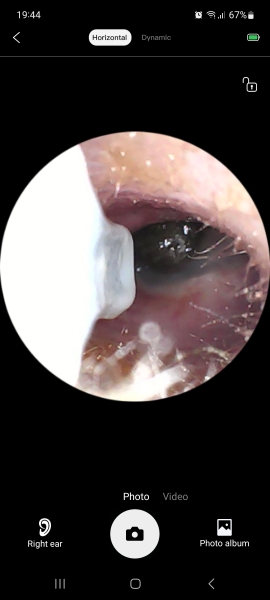

Not a happy eardrum! Also visible is the patch of damage caused by my DD4 knocking into my arm whilst the scooper was in 😬

What is it black? Is the white bit the scarring?

Just looks black because it's not a very bright light. Yeah the white bits are scarring.